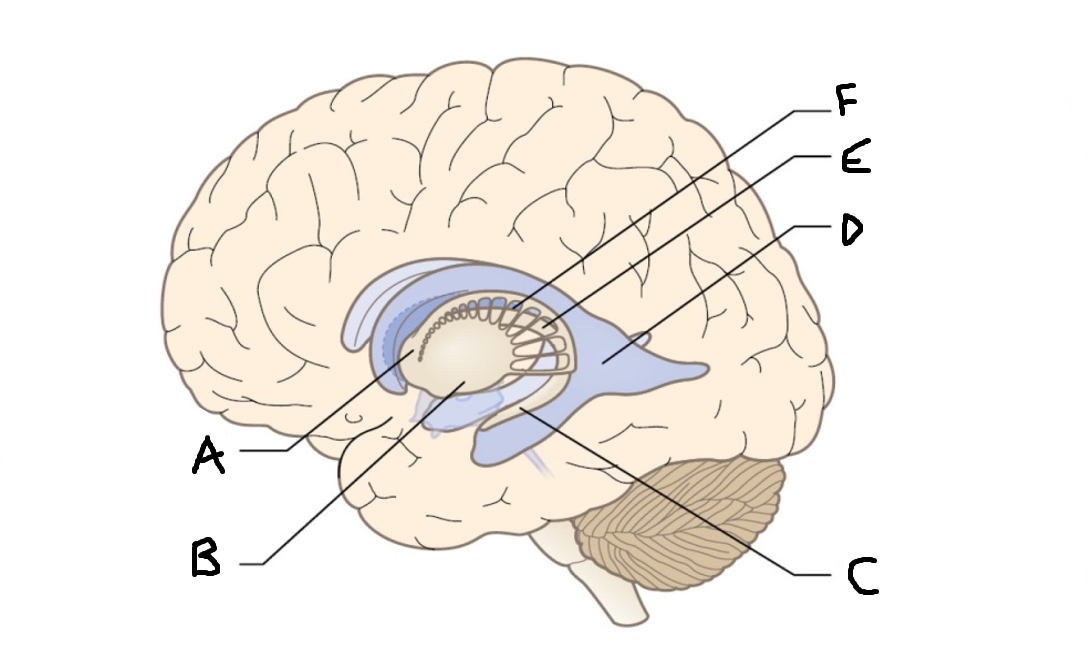

A

internal capsule (anterior limb)

B

caudate nucleus body

C

caudate nucleus head

D

putamen

E

caudate nucleus tail

F

thalamus

G

internal capsule (posterior limb)